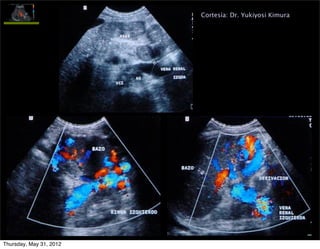

Cortesía: Dr. Yukiyosi Kimura

Signo de HP grave

(gradiente 15-28 mm

Hg)

Permeabilidad vena paraumbilical

• Colateral portosistémica (caput medusae)

• Porta izquierda  v.paraumbilical  v.pared abdominal

Importancia de su dx: 1. podría prevenir la aparición

de VE, PERO 2. riesgo EH